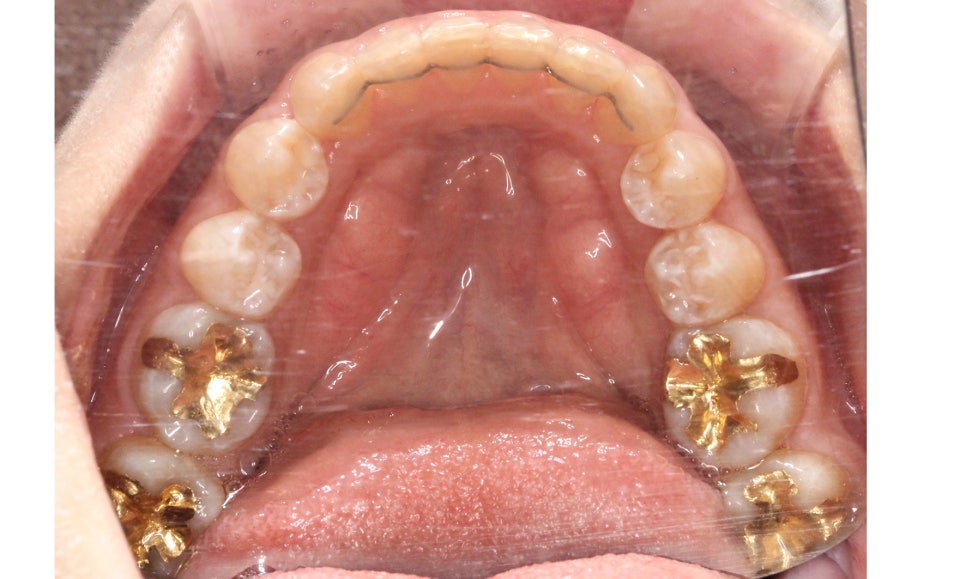

송곳니교정 전 상악의 교합면을 보면

사진에서 좌측 송곳니가 입술 방향으로

뻐드러지게 나가 있는 모습을 확인할 수 있습니다.

양악교정 후 상악 교합면을 보시면

치아의 배열이 U자에 가까운 모습으로

바뀐 것을 확인할 수 있는데요,